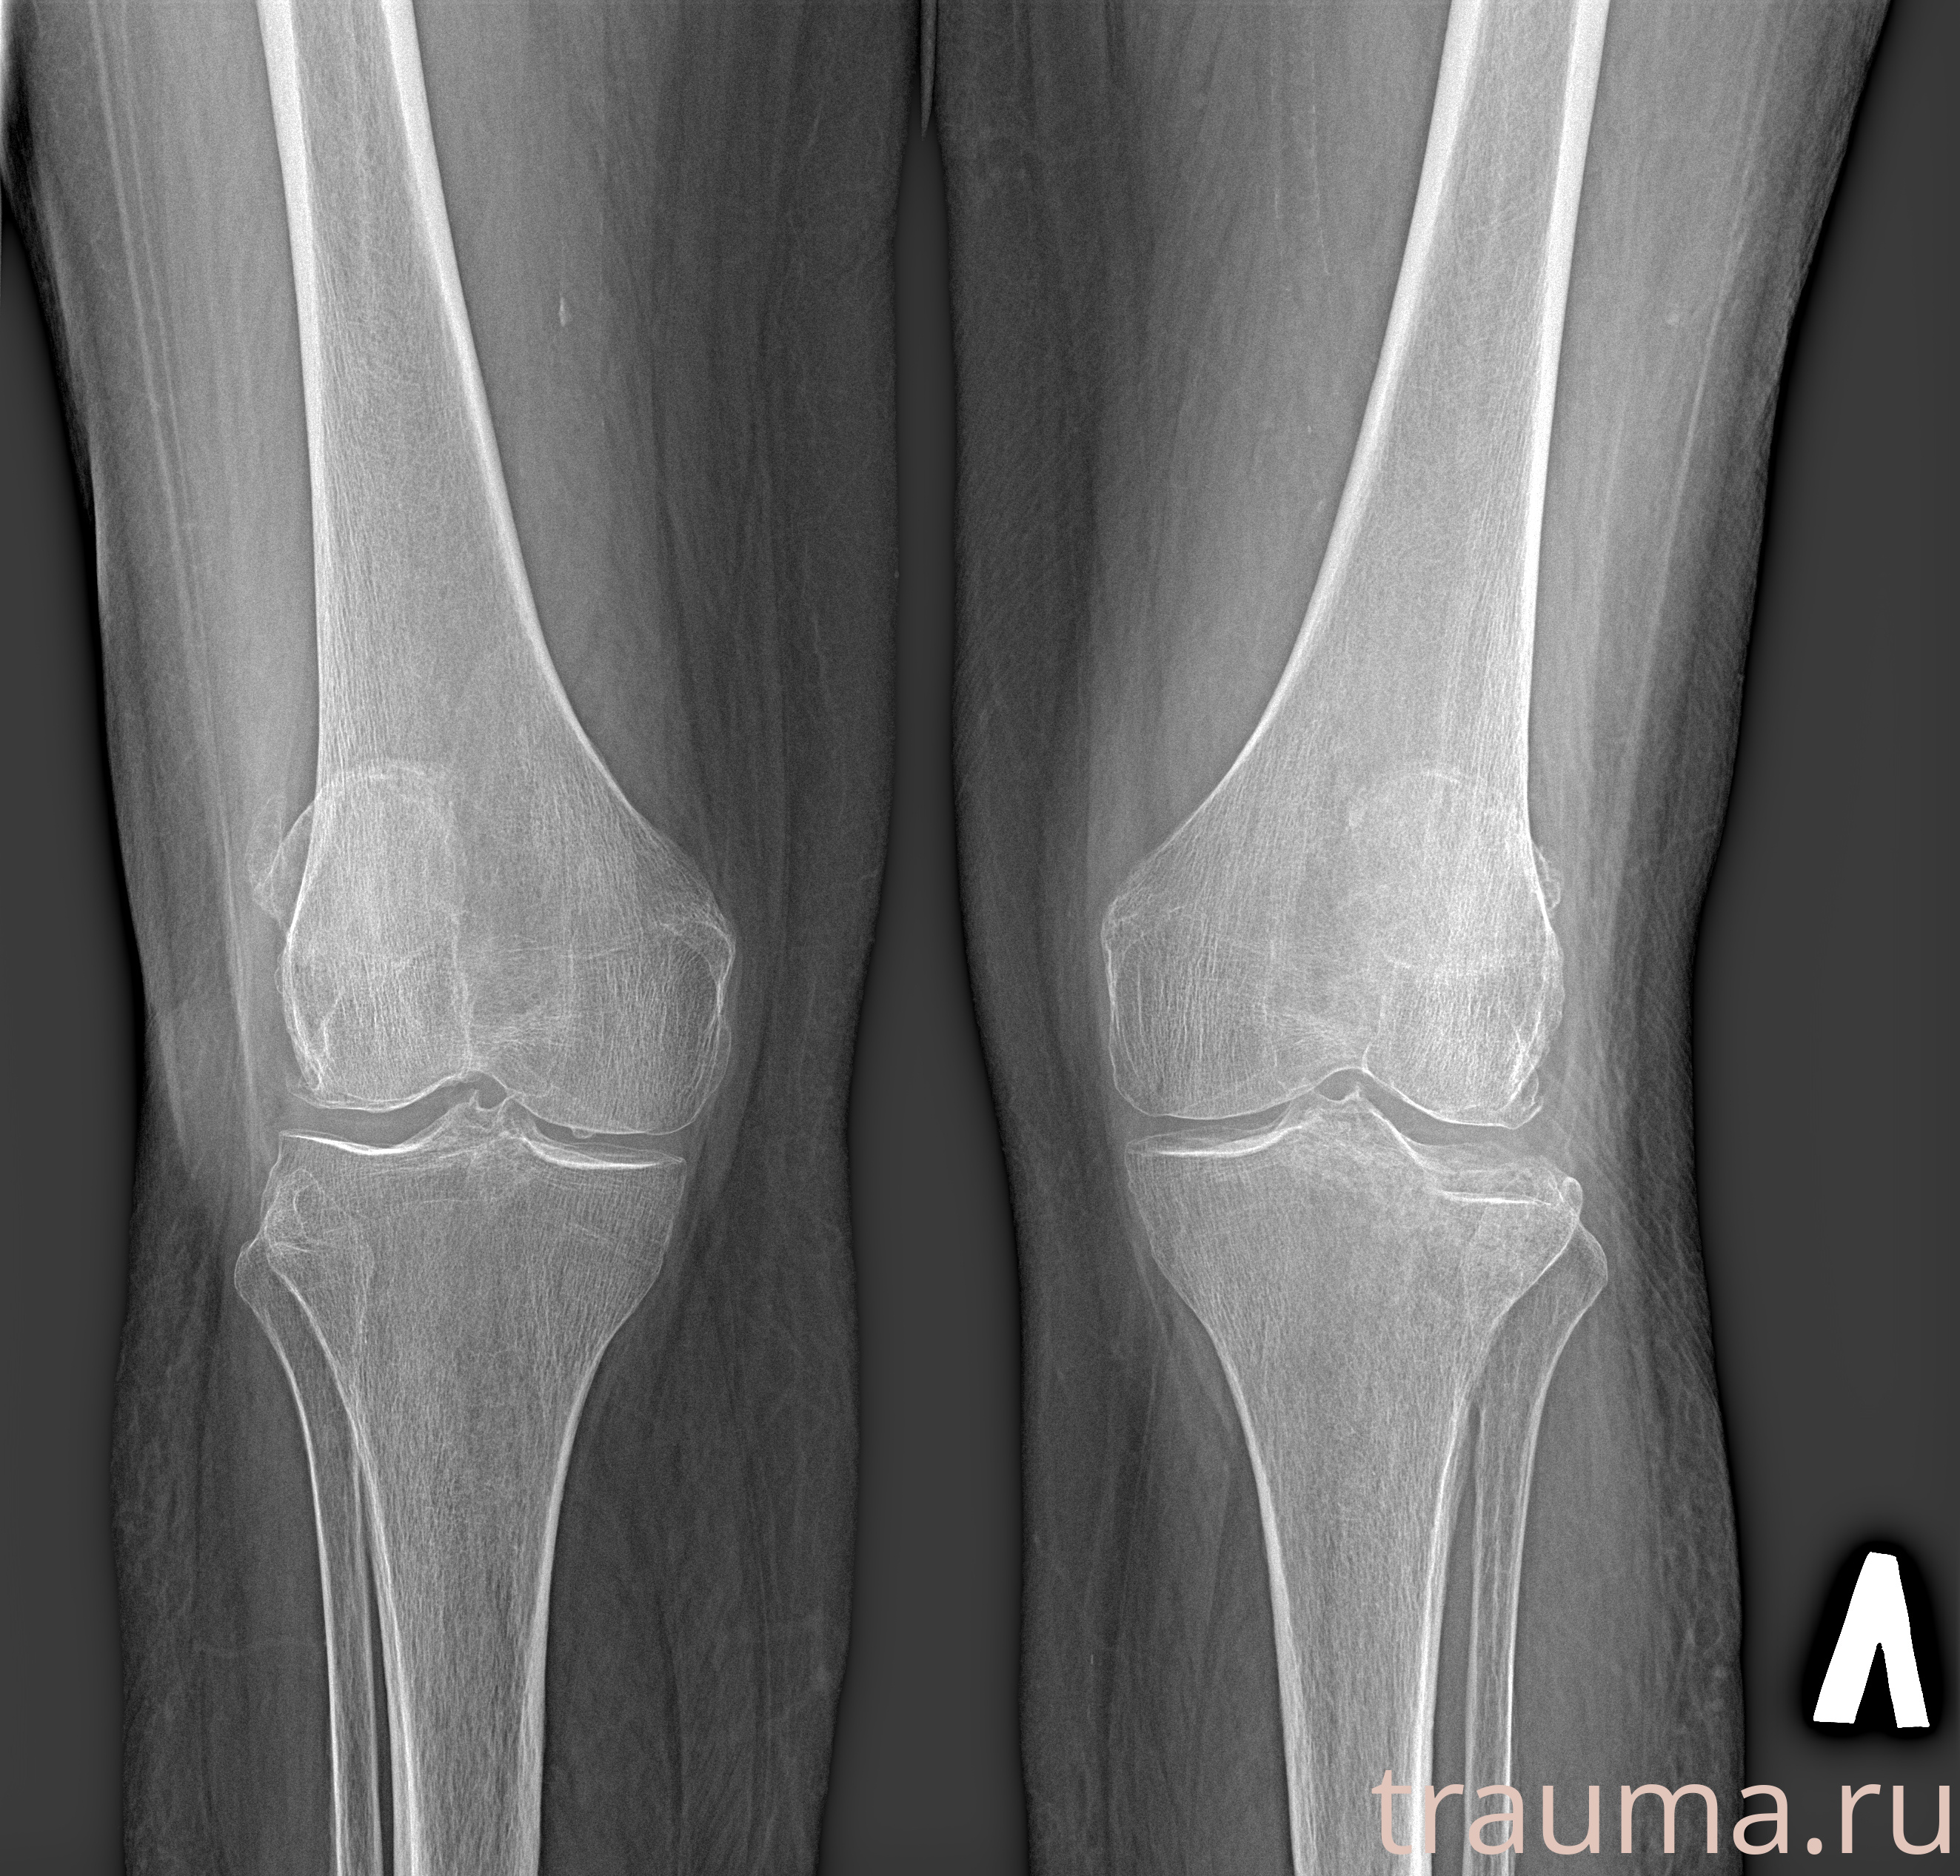

Рентгенограммы

Рентген на дому: по вашему адресу приезжает врач-рентгенолог, травматолог-ортопед с мобильным рентгеновским аппаратом, проводит диагностику травмы или заболевания, делает необходимые рентгенограммы, дает рекомендации по дальнейшему лечению. Получить качественные снимки в домашних условиях возможно благодаря уникальной методике, разработанной МосРентген Центром для института  Склифосовского